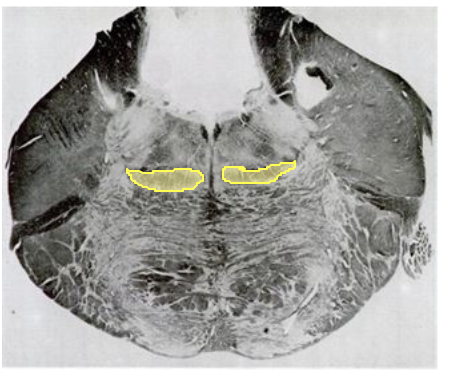

What level of brain stem is this?

What level of brainstem is this, specifically?